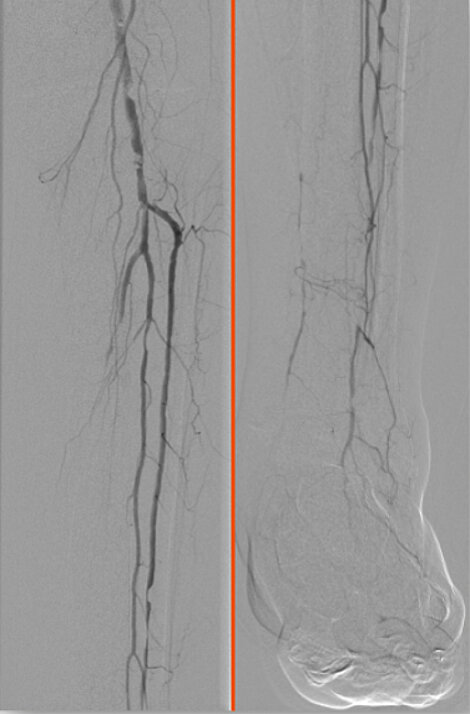

Unterschenkel- und Fußarterien bei diabetischer Angiopathie

Vorher

Verschluss der Arterie bei diabetischem Fußsyndrom (links: Unterschenkel, rechts: Fuß).

Nachher

Erfolgreiche Rekanalisation der Fußarterien.